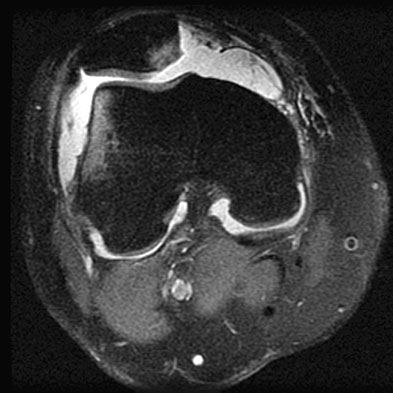

Summary Patellar instability defines a spectrum from subluxation to dislocation that results from injury, ligamentous laxity, or increased Q angle of the knee. Diagnosis is made clinically in the acute setting of a patellar dislocation with a traumatic knee effusion and in the chronic setting with passive patellar translation and a positive J sign. Treatment is nonoperative with bracing for first time dislocation without bony avulsion or presence of articular loose bodies. Operative management is indicated for chronic and recurrent patellar instability. Epidemiology Incidence 2-3% of all knee injuries annual risk of first-time patellar dislocation is 5.8 per 100,000 Demographic most commonly occurs in the 2nd-3rd decades of life Risk factors general factors ligamentous laxity (Ehlers-Danlos syndrome) previous patellar instability event recurrence rate of 15-60% following first-time dislocation risk of recurrence is 3.8 per 100,000 younger age, patella alta, and trochlear dysplasia increase the risk of recurrence "miserable malalignment syndrome" a term named for the 3 anatomic characteristics that lead to an increased Q angle femoral anteversion genu valgum external tibial torsion / pronated feet anatomical factors osseous patella alta causes patella to not articulate with sulcus, losing its constraint effects trochlear dysplasia excessive lateral patellar tilt (measured in extension) lateral femoral condyle hypoplasia muscle muscle imbalance vastus medialis oblique (VMO) muscle weakness overpull of lateral structures iliotibial band vastus lateralis Etiology Pathophysiology mechanism noncontact twisting injury with the knee extended and foot externally rotated patient will usually reflexively contract quadriceps thereby reducing the patella osteochondral fractures occur most often as the patella relocates direct blow to the medial knee less common ex. knee-to-knee collision in basketball, or football helmet to side of the knee Associated conditions medial patellofemoral ligament (MPFL) rupture most commonly disrupted at the patellar insertion in complete patellar dislocations articular cartilage damage most commonly at the medial patellar facet Anatomy Passive stability MPFL anatomy 4.5-6.4 cm long x 1.9 cm wide tensile strength of 208 N femoral origin between the medial epicondyle and adductor tubercle proximal to the superficial MCL attachment proximal and posterior to the medial epicondyle anterior and distal to the adductor tubercle patellar insertion junction of the proximal and middle thirds on the medial border of the patella undersurface of the VMO primary restraint at 0-30 degrees of knee flexion primary passive restraint to lateral patellar translation patellar-femoral bony structures account for stability in deeper knee flexion trochlear groove morphology, patella height, patellar tracking Dynamic stability provided by vastus medialis (attaches to MPFL) Classification Can be classified into the following Patellar instability classification Acute traumatic Occurs equally by gender May occur from a direct blow (ex. helmet to knee collision in football) Chronic patholaxity Recurrent subluxation episodes Occurs more in women Associated with malalignment Habitual Usually painless Occurs during each flexion movement Pathology is usually proximal (e.g. tight ITB and vastus lateralis) Trochlear dysplasia can be described by the Dejour classification types B and D more amenable to trochleoplasty Dejour Classification Dejour Type Lateral radiograph findings Axial image findings Type A Crossing sign Shallow or concave trochlea Type B Crossing sign and supratrochlear spur Flat or convex trochlea Type C Crossing sign and double contour Convex lateral facet with hypoplastic medial facet Type D Crossing sign, supratrochlear spur, and double contour Asymmetry of trochlear facets with a vertical slope/cliff pattern Presentation Symptoms complaints of instability anterior knee pain painful "pop" or "clunk" felt with patellar dislocation frequently reduces spontaneously Physical exam acute dislocation is usually associated with a large hemarthrosis 2nd most common cause of traumatic knee hemarthrosis absence of swelling supports ligamentous laxity and habitual dislocation mechanism medial sided tenderness (over MPFL) increase in passive patellar translation measured in quadrants of translation (midline of the patella is considered "0"), and also should be compared to the contralateral side normal motion is <2 quadrants of patellar translation lateral translation of the medial border of the patella to the lateral edge of the trochlear groove is considered "2" quadrants and is considered an abnormal amount of translation patellar apprehension passive lateral translation results in guarding and a sense of apprehension increased Q angle J sign excessive lateral translation in extension which "pops" into groove as the patella engages the trochlea early in flexion associated with patella alta Imaging Radiographs rule out a fracture or loose body medial patellar facet (most common) lateral femoral condyle AP views best to evaluate for malalignment and osteoarthritis lateral views best to assess for trochlear dysplasia crossing sign trochlear groove lies in the same plane as the anterior border of the lateral condyle represents flattened trochlear groove associated with patellar instability and found in 96% of patients with true patellar dislocation double contour sign anterior border of the lateral condyle lies anterior to the anterior border of the medial condyle represents convex trochlear groove/hypoplastic medial condyle supratrochlear spur arises in proximal aspect of trochlea evaluate for patellar height (patella alta vs. baja) Blumensaat's line should extend to inferior pole of the patella at 30 degrees of knee flexion Insall-Salvati method normal between 0.8 and 1.2 Blackburne-Peel method normal between 0.5 and 1.0 Caton Deschamps method normal between 0.6 and 1.3 Plateau-patella angle normal between 20 and 30 degrees Sunrise/Merchant views best to assess for lateral patellar tilt lateral patellofemoral angle (normal is an angle that opens laterally) angle between line along subchondral bone of lateral trochlear facet + most prominent aspects of anterior portion of the trochlea normal > 11° congruence angle (normal is -6 degrees) sulcus angle evaluate for trochlear dysplasia values > 140 degrees indicate flattening of the trochlea concerning for dysplasia CT scan TT-TG distance measures the distance between 2 perpendicular lines from the posterior cortex to the tibial tubercle and the trochlear groove normal values between 9 and 13 mm >20mm is highly associated with patellar instability MRI help further rule out/characterize suspected loose bodies osteochondral lesion and/or bone bruising medial patellar facet (most common) lateral femoral condyle evaluate MPFL and medial retinaculum tear frequently at the medial patellar insertion Adult Treatment Nonoperative NSAIDS, activity modification, and physical therapy indications mainstay of treatment for first time patellar dislocator without any loose bodies or intraarticular damage habitual dislocator techniques short-term immobilization for comfort followed by 6 weeks of controlled motion emphasis on strengthening closed chain short arc quadriceps exercises quad strengthening core and hip strengthening to improve limb positioning and balance (hip abductors, gluteals, and abdominals) patellar stabilizing sleeve or "J" brace consider knee aspiration for tense effusion positive fat globules indicate fracture Operative Arthroscopic debridement (removal of loose body) vs Repair with or without stabilization indications displaced osteochondral fractures or loose bodies can be an indication for operative treatment in a first-time dislocator techniques arthroscopic vs open removal versus repair of the osteochondral fragment primary repair with screws or pins if sufficient bone available for fixation MPFL repair indications acute first-time dislocation with bony fragment techniques direct repair when surgery can be done within first few days no clinical studies support this over nonoperative treatment MPFL reconstruction with autograft or allograft indications recurrent instability no significant underlying malalignment techniques gracilis or semitendinosus commonly used (stronger than native MPFL) femoral origin can be reliably found radiographically (Schottle point) 1 mm anterior to the posterior femoral cortex, 2.5 mm distal to the adductor tubercle, and proximal to Blumensaat's line a femoral tunnel positioned too proximally results in graft that is too tight ("high and tight") in pediatric patients, the femoral side should be secured more anterior/distal to Schottle's point outcomes severe trochlear dysplasia is the most important predictor of residual patellofemoral instability after isolated MPFL reconstruction rate of recurrent instability does not differ with regard to graft choice (allograft vs. autograft vs. synthetic graft) Fulkerson-type osteotomy (anterior and medial tibial tubercle transfer) indications may be used with or without MPFL reconstruction for significant malalignment TT-TG >20mm on CT techniques anteromedialized displacement of osteotomy and fixation patellofemoral contact pressures increased proximally and medially correct TT-TG to 10-15mm (never less than 10mm) tibial tubercle distalization indications patella alta techniques distal displacement of osteotomy and fixation lateral release/lengthening indications isolated release no longer indicated for patellainstability may lead to iatrogenic medial instability lateral lengthening has shown better outcomes, less quadriceps atrophy, and lower incidence of medial patellar instability only indicated if there is excessive lateral tilt or tightness after medialization technique arthroscopic trochleoplasty indications rarely addressed (in the USA) even if trochlear dysplasia present severe dysplasia recent literature reports that Dejour types B and D are most amenable to trochleoplasty revision cases with residual patellar instability techniques arthroscopic or open sulcus deepening procedure open recession wedge trochleoplasty guided growth (temporary hemiepiphysiodesis) indications in those with genu valgum greater than 10° and patellar instability and at least six months of growth remaining techniques tension band (8-plate) staples believed to be more rigid, providing faster correction Pediatric Treatment Same principles as adults in general but must preserve the physis tibial tubercle osteotomy contraindicated (will harm growth plate of proximal tibia) Complications Recurrent dislocation redislocation rates with nonoperative treatment may be high (15-60%) at 2-5 years recurrence rate is highest in those patients who sustain a primary dislocation under the age of 20 Medial patellar dislocation and medial patellofemoral arthritis almost exclusively iatrogenic as a result of prior patellar stabilization surgery Inferolateral anterior knee numbness damage to the infrapatellar branch of the saphenous nerve during the midline skin approach to TTO